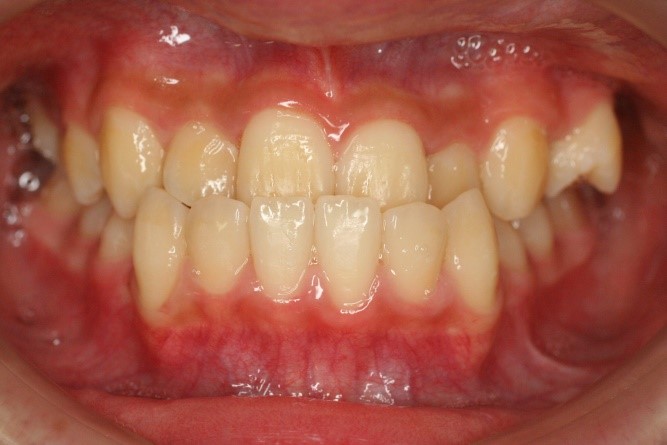

症例02|20代の男子

前歯部の反対咬合の症例

上下の前歯が反対咬合を主訴として来院されました。通常通り検査を行い「反対咬合」と診断されました。

治療計画

下の犬歯から後ろの歯をまずは後方に移動して、その後に上下の歯並びを綺麗に並べて前歯部の咬み合わせを改善することにしました。

矯正の種類

カリエールディスタライザー、上に裏側、下に表側のセラミック(白い矯正装置)

治療前の写真を治療後の写真を比べると、鼻の下がくぼんでいたのが改善されて口元が綺麗になった事が解ります。また歯並びは綺麗に並び上の歯が前に出て下の歯が後ろに移動して歯がしっかりと咬み合っています。

患者様に協力いただけたため、2年の治療期間で終了することができました。